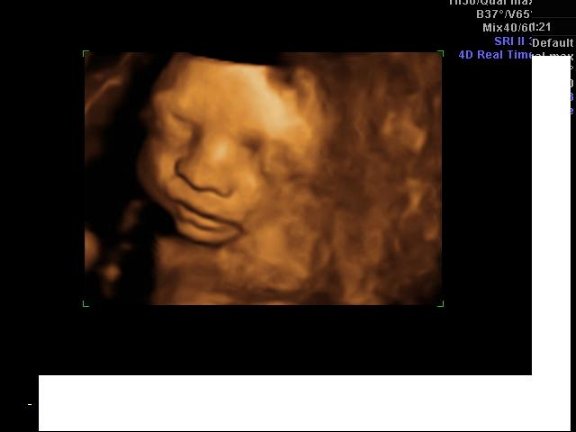

Egy bizonyíték a kukira: Kép

Nagyon szép lett Milán szobája! Ügyes vagy! A kissrác büszke lesz az anyukájára! :) A 4D-s képek! :):):) Szuperek! Milánnak olyan szép kis arcocskája van, hogy csak csuda! :) Nagyon szép! :)